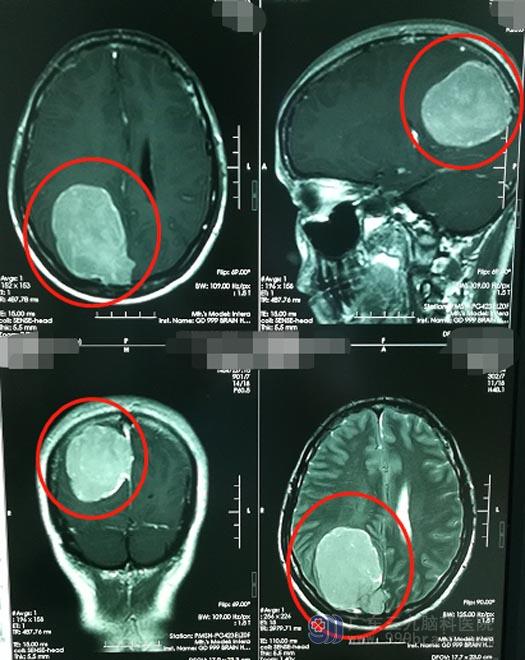

顺利入住神经外五科后,医院副院长、神经外五科主任鲁明详细询问了病情,对罗女士进行了进一步的检查,头颅MRI检查显示:右侧顶部镰旁占位性病变,大小约6.3cm×5.7cm×4.9cm,病变突入上矢状窦,已形成右侧大脑镰下疝,右侧海马钩回疝。

肿瘤巨大,并且已经突入上矢状窦,这是很凶险的。矢状窦大脑镰旁脑膜瘤是指肿瘤基底附着于矢状窦、大脑镰并充满矢状窦角的脑膜瘤,由于肿瘤生长过大,同时侵犯上矢状窦和大脑镰,临床称之为“窦镰旁脑膜瘤”。由于瘤体大、位置深,多累及颅内大血管或静脉窦,增加了手术风险和难度,被迫残留部分肿瘤又可导致术后复发;手术中既要妥善处理受累的上矢状窦和大脑镰,同时还要保护好中央区脑组织和中央沟静脉,矢状窦是大脑静脉回流的地方,一旦术中碰触了矢状窦,是很难止住血的,所以,矢状窦一直以来被称为“神经外科手术的禁区”。